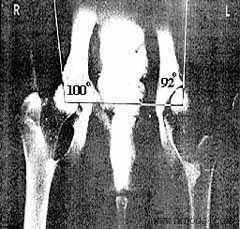

4. Шеечно-диафизарный угол

образуется пересечением осей шейки и

диафиза (тела) бедренной кости.

Дисплазия 2 степени:

- угол Норберга менее 100 градусов;

- отчетливые напластования на шейке

бедренной кости;

- слабая фиксация головки бедра или

ее незначительная деформация;

- несколько уплощенная суставная

впадина.